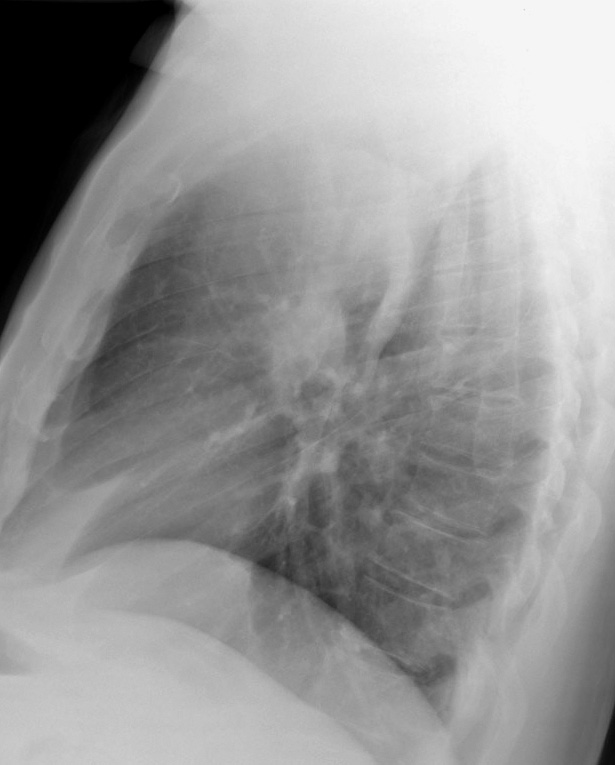

RUL Collapse Case 1 Lateral